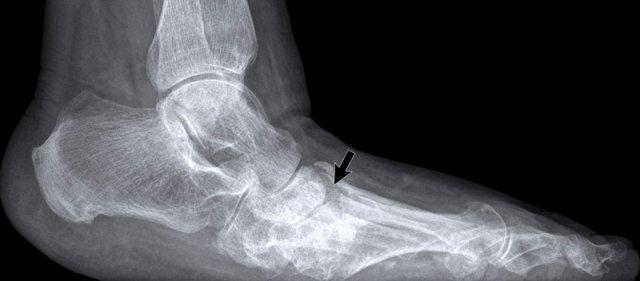

Tổn thương điển hình tại khớp MTP1 với bào mòn dạng “đục lỗ”.

Sưng mô mềm biểu hiện cho hạt tophi.

Trật khớp không phải là dấu hiệu thường gặp trong gout, nhưng trong trường hợp này là hậu quả của các bào mòn và tổn thương dây chằng.

Tỷ trọng mô mềm

Sưng mô mềm tăng tỷ trọng điển hình bao quanh khớp MTP1 hai bên.

Bào mòn cạnh khớp ở mặt trong của đầu xương bàn chân (MT) phía xa, có viền xơ cứng.

Tổn thương rõ nhất ở bên phải (mũi tên).